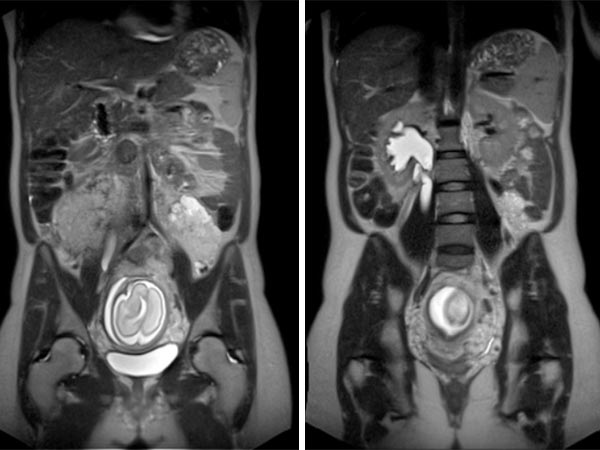

Coronal (top) and axial (bottom) T2-weighted, fat-suppressed MR sequences without contrast at baseline before pregnancy.

Coronal (top) and axial (bottom) T2-weighted sequences without contrast at 21 weeks' gestation.

Marked increase in size of the VM during pregnancy, which is visualized ventrally of the left psoas muscle as a signal-intense lesion, without displacement or compression of the placenta.

Coronal T2 sequences depicting progression of the VM ventrally sitting on the left psoas muscle at 21 weeks’ gestation. During pregnancy, the patient also develops grade 3 right-sided hydronephrosis.

In the axial T2-HASTE sequence at 21 weeks' gestation, the VM is adjacent to the placenta without displacement of the uterus or fetus.